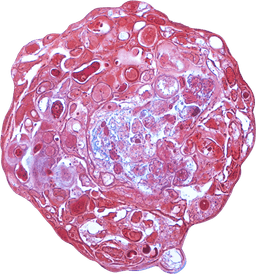

VitroScreen, a SenzaGen Group company, pioneers next-generation in vitro testing solutions. We leverage cutting-edge biological models—from 2D cells and reconstructed tissues to ex vivo systems and cellular spheroids—to deliver precise, human-relevant data for the Cosmetics, Medical devices, Nutraceuticals, Pharma and Chemicals industries.

Our models mirror human biology for precise, predictive accuracy.

We design and execute rigorous preclinical in vitro studies, combining validated testing standards with fully customized protocols to deliver reproducible, decision-ready results. Our expertise covers multiple product categories and therapeutic areas, providing highly predictive platforms for both regulatory and efficacy assessment.